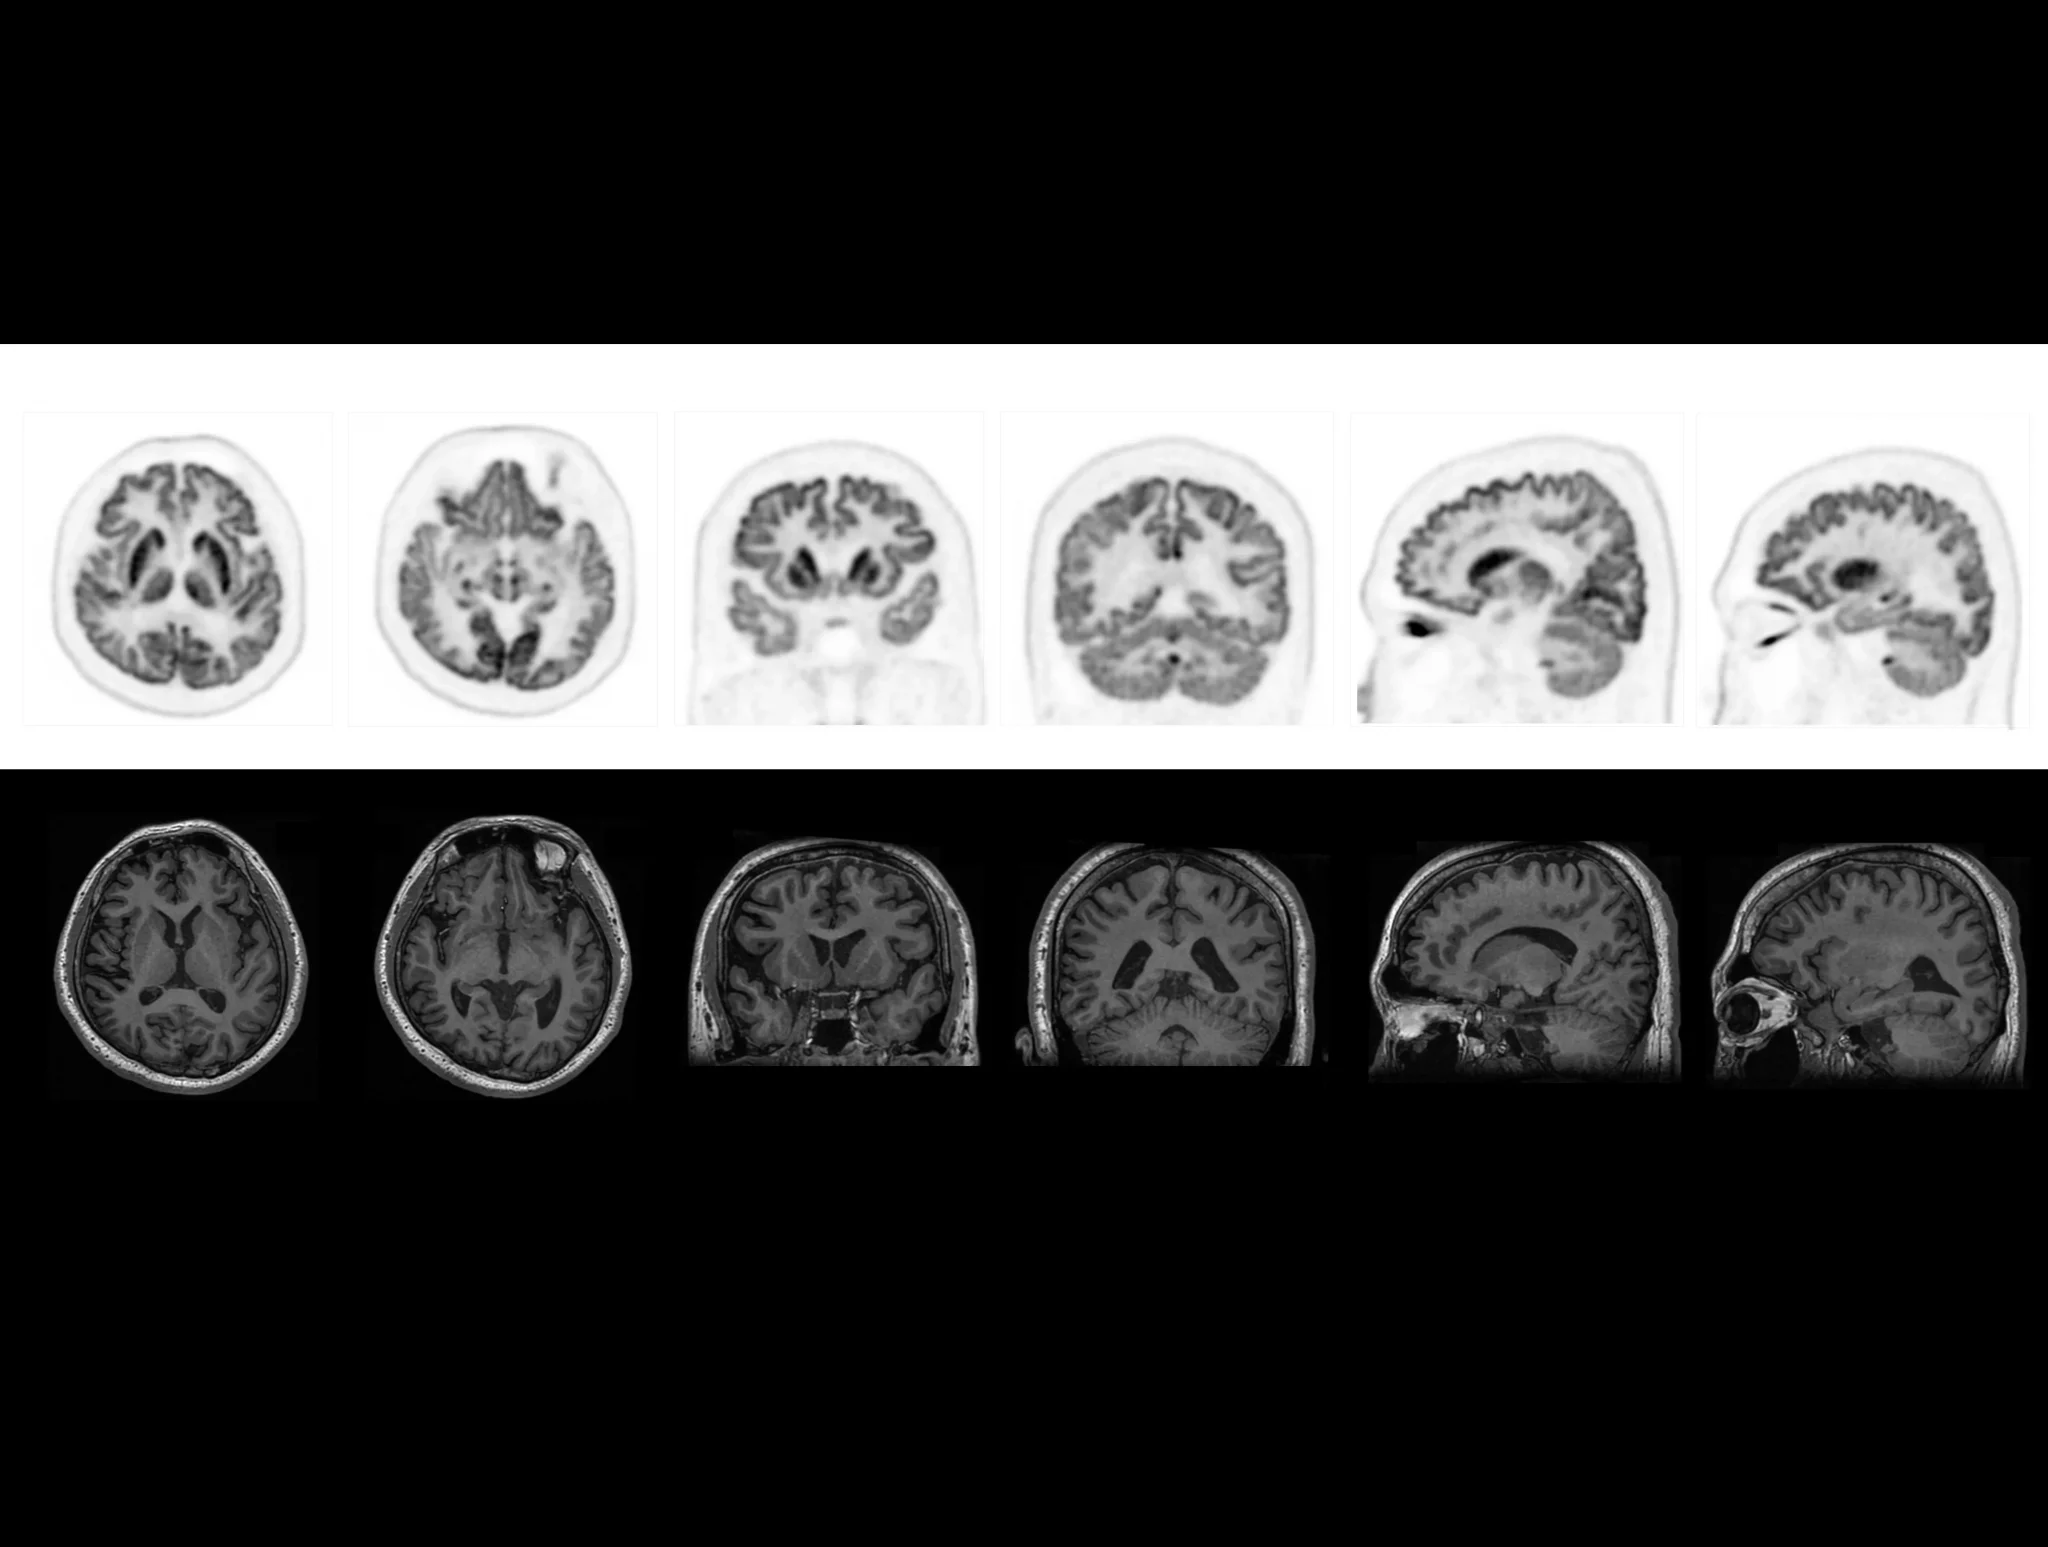

uMI Panorama is clearly magnificent in every direction with the finest National Electrical Manufactures Association (NEMA) PET spatial resolution, truly-fast 189-picosecond (ps) time of flight (TOF), scalable axial field of view (AFOV), the 76-cm super-wide bore and 318-kg (700-lb) table weight capacity that accommodates patients of all sizes.1 By leveraging the AI-powered features on the uExcel platform, it also boosts your daily work efficiency significantly and opens up new possibilities for your exploration.

Venture beyond traditional boundaries and embrace a future of breakthroughs with uMI Panorama. It delivers consistently high performance across different tracers or concentrations, supporting versatile clinical or research applications to meet your needs today and tomorrow.

With the ultra-high system performance, uMI Panorama faces up to the challenges of tracers with different half lives and the complex scanning conditions, without compromise for image quality.